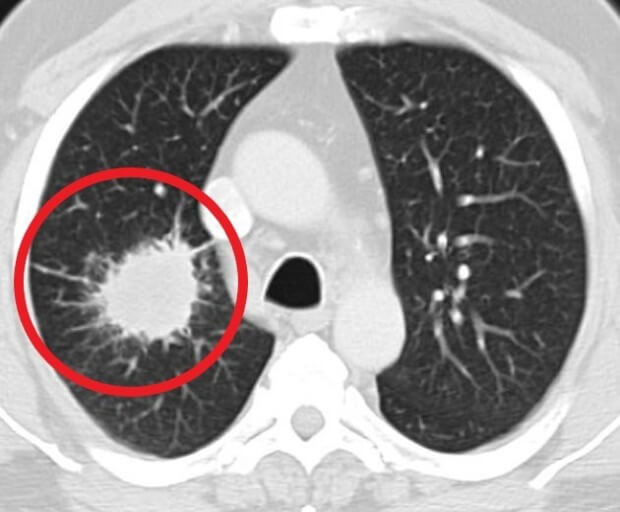

숨 쉬는 순간마다 위협하는 무서운 적, 폐암. 전체 암 사망 원인 1위를 차지하며, 진단 후 5년 내 사망률이 7~80%에 달하는 치명적인 질병입니다. 하지만 조기 발견 시 90%라는 놀라운 완치율을 기대할 수 있다는 사실, 알고 계셨나요?

폐암은 초기에는 증상이 나타나지 않기 때문에 진단하기 어려운 암입니다. 그러나 폐암이 진행됨에 따라 다음과 같은 증상이 나타날 수 있습니다.